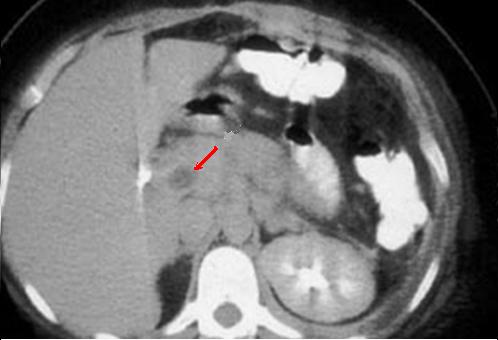

Epaissisement

stenosante de la paroi du colon descendante , Image

radiologique TDM en coupe coronale d'une colite

ischemique |

|

Epaissisement de la paroi du colon

d'une colite ischemique du colon transverse . Image

radiologique TDM en coupe axiale . |